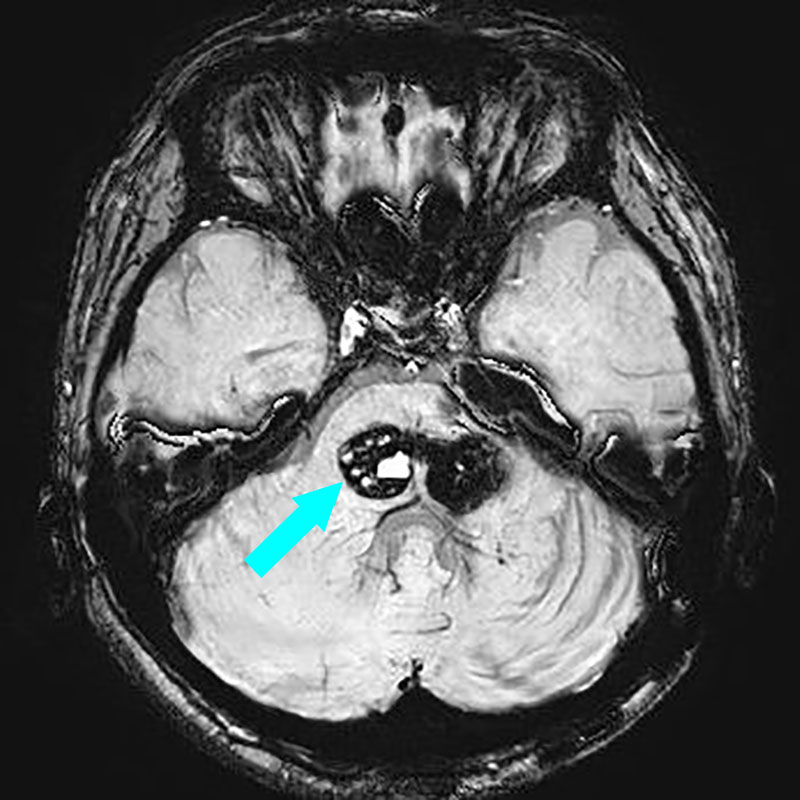

小脳

出血性海綿状血管腫

再出血の予防目的

大阪府の病院より紹介

Lt-supracerebellar

infratentorial

approach

No.No.53 手術前1

No.No.53 手術前2

No.No.53 手術後1

No.No.53 手術後2

CT/MRにより完全に摘出されたことが確認された